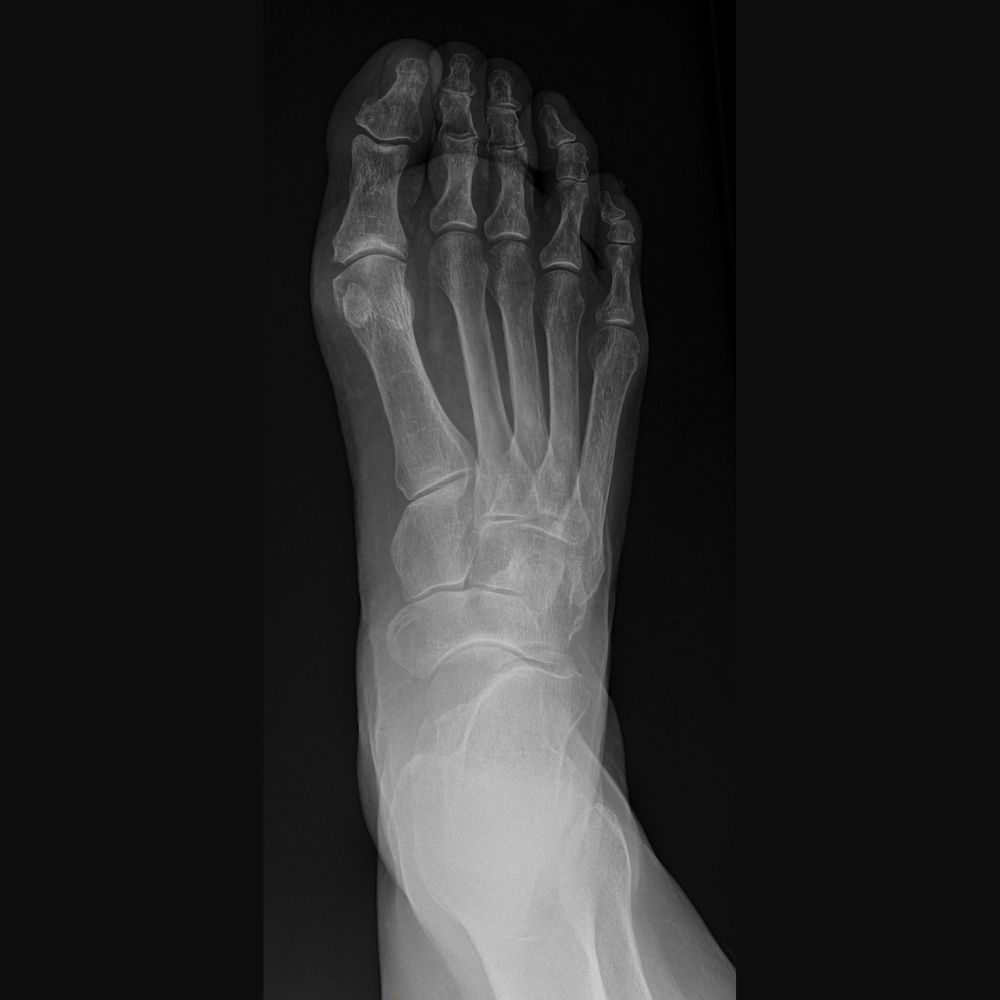

Adult with Fusion (Arthrodesis) of the Left Hallux Rigidus (Osteoarthritis of the Big Toe)